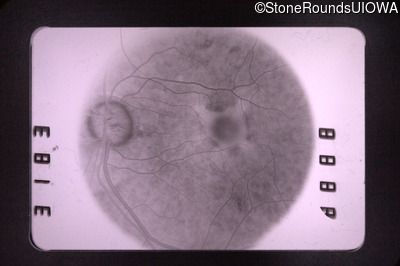

Fluorescein Angiography - Left - 20/40 +3

Exemplar